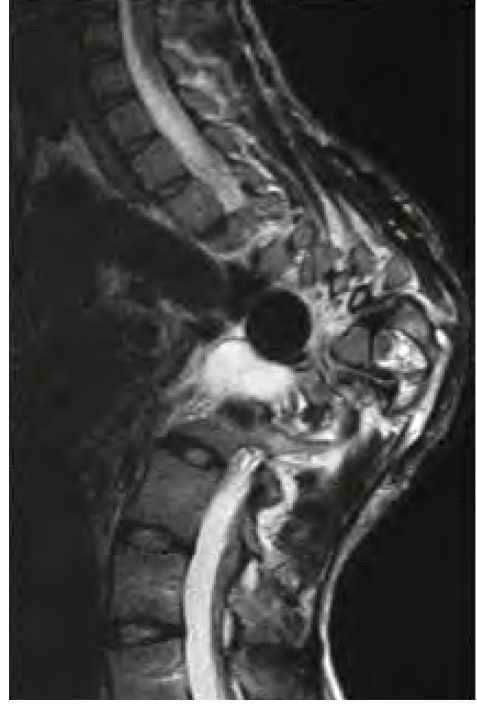

בנוירופיברומטוזיס מסוג 1 קיימות פגיעות שלדיות רבות. המעורבות הגרמית היא לרוב קלה ולעתים אף מהווה קריטריון אבחנתי למחלה, כמו למשל דיספלזיה (Dysplasia) של עצם היתד (Sphenoid) (תמונה 6) או אי חיבור (Pseudoarthrosis) של עצם השוקה (Tibia) (תמונה 7). בעיות שכיחות יותר הן קומה נמוכה (כ-30%) ועקמת (כ-10%). לעתים נצפים מקרים קשים של עקמת ועקשת (Kyphoscoliosis) המחמירים במהלך החיים ומסכנים את תפקוד הריאות והלב ודורשים התערבות ניתוחית (תמונה 8). כ-50% מהמבוגרים עם נוירופיברומטוזיס מסוג 1 מפתחים ירידה בצפיפות העצם (Osteoporosis) וזקוקים לאבחון וטיפול תרופתי בהתאם.